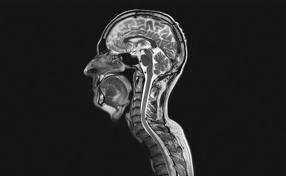

核磁共振成像是隨著計算機技術、電子電路技術、超導體技術的發展而迅速發展起來的一種生物磁學核自鏇成像技術。它是利用磁場與射頻脈衝使人體組織內進動的氫核(即H+)發生章動產生射頻信號,經計算機處理而成像的。原子核在進動中,吸收與原子核進動頻率相同的射頻脈衝,即外加交變磁場的頻率等於拉莫頻率,原子核就發生共振吸收,去掉射頻脈衝之後,原子核磁矩又把所吸收的能量中的一部分以電磁波的形式發射出來,稱為共振發射。共振吸收和共振發射的過程叫做“核磁共振”。核磁共振成像的“核”指的是氫原子核,因為人體的約70%是由水組成的,MRI即依賴水中氫原子。當把物體放置在磁場中,用適當的電磁波照射它,使之共振,然後分析它釋放的電磁波,就可以得知構成這一物體的原子核的位置和種類,據此可以繪製成物體內部的精確立體圖像。通過一個磁共振成像掃描人類大腦獲得的一個連續切片的動畫,由頭頂開始,一直到基部。

頭部核磁共振檢測人腦是如何思想、感受的,至今仍一直是個謎。而且是科學家們關注的重要課題。而利用MRI的腦功能成像則有助於我們在活體和整體水平上研究人的思維。其中,關於盲童的手能否代替眼睛的研究,是一個很好的樣本。正常人能見到藍天碧水,然後在大腦里構成圖像,形成意境,而從未見過世界的盲童,用手也能摸文字,文字告訴他大千世界,盲童是否也能“看”到呢?專家通過功能性MRI,掃描正常和盲童的大腦,發現盲童也會像正常人一樣,在大腦的視皮質部有很好的激活區。由此可以初步得出結論:盲童通過認知教育,手在某種意義上,是可以代替眼睛“看”到外面世界的。